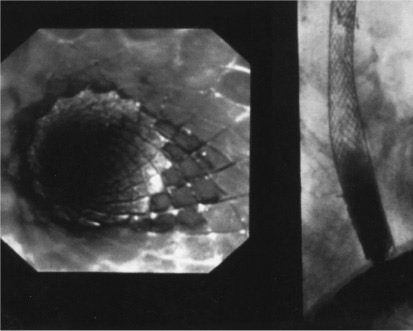

Dilatação/Colocação de Prótese.

A dilatação de estenoses tumorais para paliar a disfagia e permitir a avaliação por USE está associada a risco de ruptura esofagiana ou sangramento de 2% a 3%.

Infelizmente, o alívio permanece por apenas algumas semanas.

A visão endoscópica de prótese recoberta após colocação (esquerda) mostra a patência da prótese no estudo contrastado (direita).

Os pacientes com estenoses malignas de alto grau mais frequentemente apresentam doença avançada.

O objetivo da colocação de prótese é:

- atravessar a obstrução no esôfago

- permitir, primariamente, a patência luminar para:

- controle da saliva

- ecundariamente, para nutrição.

Próteses auto-expansíveis e flexíveis são construídas em duas camadas de uma superliga de fio monofilamentar, com uma camada de silicone entre ambas. O silicone interposto às camadas retarda o crescimento tumoral através dos orifícios do aramado.

Após a administração de anestesia local ou geral, a estenose é dilatada a 42 ou 45 French, a lesão é identificada, e a prótese recoberta e expansível é colocada sob controle endoscópico e fluoroscópico. Uma vez que a prótese é inserida e expandida, os rebordos são ancorados à parede esofágica.

Os pacientes percebem desconforto torácico inicial pela distensão da estenose. A inserção de próteses metálicas auto-expansíveis não impede tratamento posterior com quimioterapia ou radioterapia. Apesar da melhora do paciente em deglutir saliva, a ingestão oral deve se restringir a alimentos que passam através de uma prótese esofagiana rígida.

A média de sobrevida após a colocação de uma prótese para carcinoma esofágico é inferior a 6 meses.

Esta modalidade terapêutica é também adequada a pacientes com fístula traqueoesofágica, quando a prótese intraesofágica pode tanto ocluir a fístula quanto permitir a alimentação via oral por vários meses.